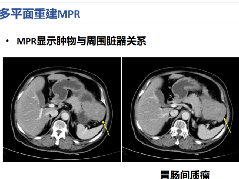

CT urogram (2017): Noncontrast images demonstrate multiple bilateral nonobstructing renal calculi, the largest measuring 6 mm in the right kidney. Some of the calcifications could represent nephrocalcinosis — for example, those in the upper pole of the right kidney. The kidneys show symmetric enhancement without suspicious renal mass. Multiple bilateral exophytic simple renal cysts are noted, the largest in the midpole of the right kidney measuring 3.6 x 4.3 cm. There are additional subcentimeter low-attenuation lesions that are too small to characterize. There is a “paintbrush sign” appearance to the renal medullae in keeping with a history of medullary sponge kidney. There is mild bladder wall thickening and trabeculation that may be related to chronic outlet obstruction. Further evaluation is deferred to cystoscopy.

CTU:CT平扫可见双肾多发非梗阻性肾结石,右肾最大者直径约6mm,其中一些钙化可能代表肾结石,例如,右肾上极的那些。肾脏对称性强化,未见可疑肾肿物。双肾可见多发单纯性肾囊肿,大者位于右肾中部,大小约3.6 x 4.3 cm;另可见不足1cm的低密度灶,其太小而不能显示。肾髓质表现为“毛刷征”,符合髓质海绵肾。膀胱壁轻度增厚并小梁形成,与慢性流出道梗阻有关。进一步评估需膀胱镜检查。